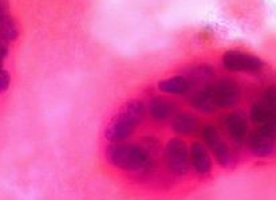

The researchers at VTT used RNA interference-based screening in breast cancer cells and found that an enzyme that modifies heparan sulfate glycosaminoglycans, HS6ST2, is an important regulator of breast cancer cell-bone interactions.